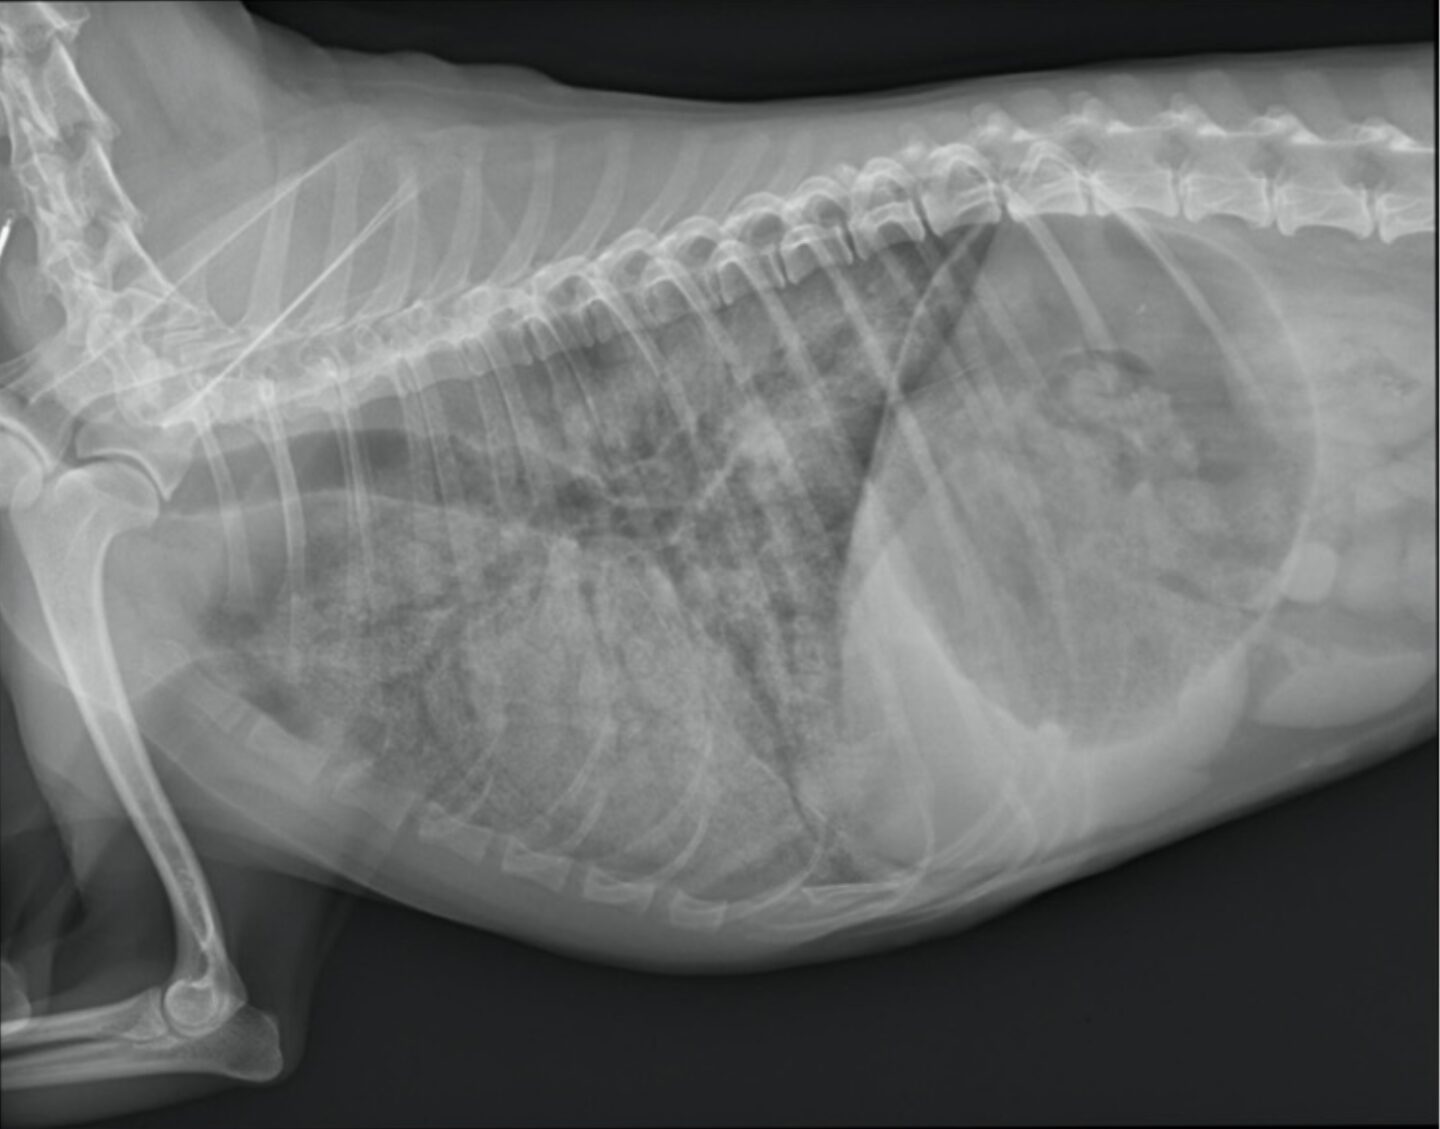

Die Leptospirose ist eine nahezu weltweit vorkommende Zoonose und kann eine Vielzahl von Lebewesen befallen: Infektionen sind bei über 150 Säugetieren, bei Reptilien, Fischen und Amphibien beschrieben – sie alle stellen ein potentielles Reservoir für Infektionen bei Menschen da. Für Tierärzte ist die Infektion beim Hund die relevanteste, da es hier zu schweren und lebensbedrohlichen Verläufen kommen kann.